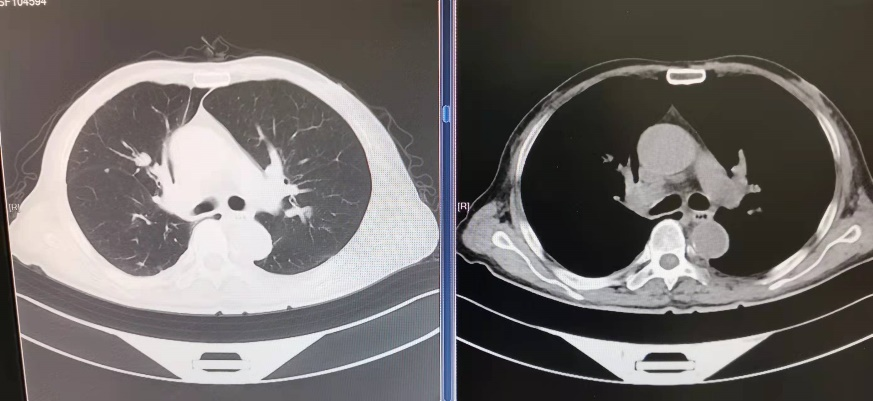

70岁的吴先生近2个月出现胸闷、气喘症状,最近几天轻微活动就有症状加重,乏力、纳差明显,一般情况不佳。外院胸部CT可见气管、右主支气管内软组织影,右上肺不张。患者既往有肾恶性肿瘤病史,伴全身多处转移,因此考虑到气道内软组织为肾癌转移所致。该患者先在上海就诊,后辗转昆山、苏州市内等多家三甲医院,均未解决气道阻塞的问题。由于当时疫情严重,呼吸科作为高风险专科,苏州地区所有医院的普通气管镜诊疗活动全部暂停。

术前CT可见气管下端及右主支气管新生物阻塞管腔

术后CT见梗阻解除,气道通畅